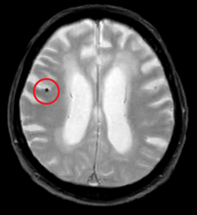

・無症候性脳梗塞(ラクナ梗塞)

症状がなくても脳の血管が詰まることがあり、将来の脳卒中や認知症のリスクを高めます。

実際の異常所見

![]() 無症候脳梗塞 |

無症状でもこのような所見がみられることがあります。このように早期で発見し適切な対策を行うことで、病気の進行を遅らせたり、予防することが可能になります。